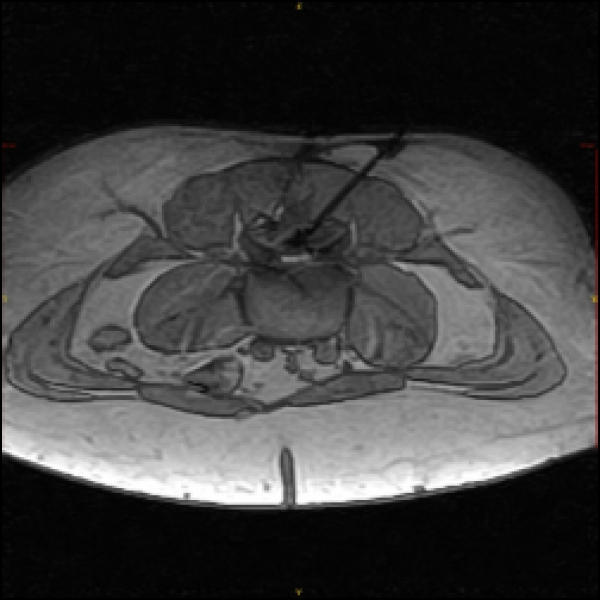

Beim akuten wie auch beim chronischen Bandscheibenvorfall werden entzündungshemmende Medikamente in die unmittelbare Nähe des Bandscheibenvorfalls und des Entzündungsprozesses injiziert. Die Entzündung klingt ab und die Schwellung wird geringer.

Daher bedarf der Bandscheibenvorfall heute nur selten einer klassischen Operation, um ihn erfolgreich zu behandeln und Schmerzfreiheit zu erreichen. Im Gegenteil, da nach Operationen die Gefahr von Verwachsungen und damit verbundenen oft lang anhaltenden starken Beschwerden recht hoch ist, sollte ein operativer Eingriff nur bei Lähmungserscheinungen oder bei nicht durch konservative Therapie zu bessernde Beschwerden in Erwägung gezogen werden.